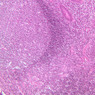

Diffuse Lymphatic Tissue and Nodules

The visceral walls have concentrations of lymphoid tissues that comprise the body's filters against foreign organisms that attempt to enter by way of the alimentary, urinary, or respiratory tracts. The lamina propria is a layer of connective tissue underlying the epithelium of mucous membranes; lymphatic tissue is often found in the lamina propria. This lymphatic tissue can assume three forms; 1) diffuse lymphatic tissue, 2) solitary lymphatic nodules, and 3) aggregated lymphatic nodules. The simplest arrangement of lymphoid tissue occurs as diffuse patches of lymphocytes scattered in the lamina propria of the walls of visceral organs. When a patch becomes activated by antigens or foreign organisms, it takes on the appearance similar to a nodule in the cortex of a lymph node (see below). These nodules are not encapsulated and simply occur in the visceral wall as an accumulation of lymphocytes, macrophages, and plasma cells embedded in reticular tissue. Eosinophilic leukocytes are frequently seen.

Examine sections B-12 (jejunum, H&E [2.5x, 10x-labeled, 20x, 40x]); B-16, ileum, H&E [2.5x-labeled, 10x, 20x]; B-18, ileum, H&E [2.5x, 10x-labeled, 20x, 40x]; B-20, appendix, H&E [2.5x, 10x-labeled, 20x, 40x-labeled]) and find examples of diffuse lymphatic tissue. Solitary nodules of lymphoid tissue as well as diffuse lymphoid tissue can be found almost anywhere along the gastrointestinal system (this is sometimes called GALT, gut associated lymphoid tissue). The most noted areas with aggregated nodules are found in ileum—Peyer’s Patches (slide B-18, H&E [2.5x-labeled, 10x-labeled, 20x, 40x] [2.5x, 10x, 20x, 40x]), and appendix (slide B-20, H&E [2.5x, 10x, 20x, 40x] [2.5x, 10x,20x, 40x] [2.5x-labeled, 10x, 20x-labeled, 40x]). Peyer's Patch consists of aggregated nodules of lymphoid tissue. Compare the appearance of Peyer's patches to the lymphoid tissue in the appendix. In the appendix, the lymphoid tissue of the appendix appears as a continuous ring of lymphatic tissue in the lamina propria. What features differentiate the appendix from the Ileum?

In lymphatic nodules and nodes the term primary nodule refers to a nodule of homogeneously, tightly packed small lymphocytes. When lymphatic nodules have germinal centers they are called secondary nodules. A germinal center contains lighter staining, "B" lymphocyte precursors. Mitotic figures should be easily spotted in the core of the nodule. Compare these cells with the mass of small more differentiated lymphocytes that surround the germinal center. Some of these lymphocytes are cytokine producing T-Helper cells that are stimulating the proliferation of the lymphoblasts.